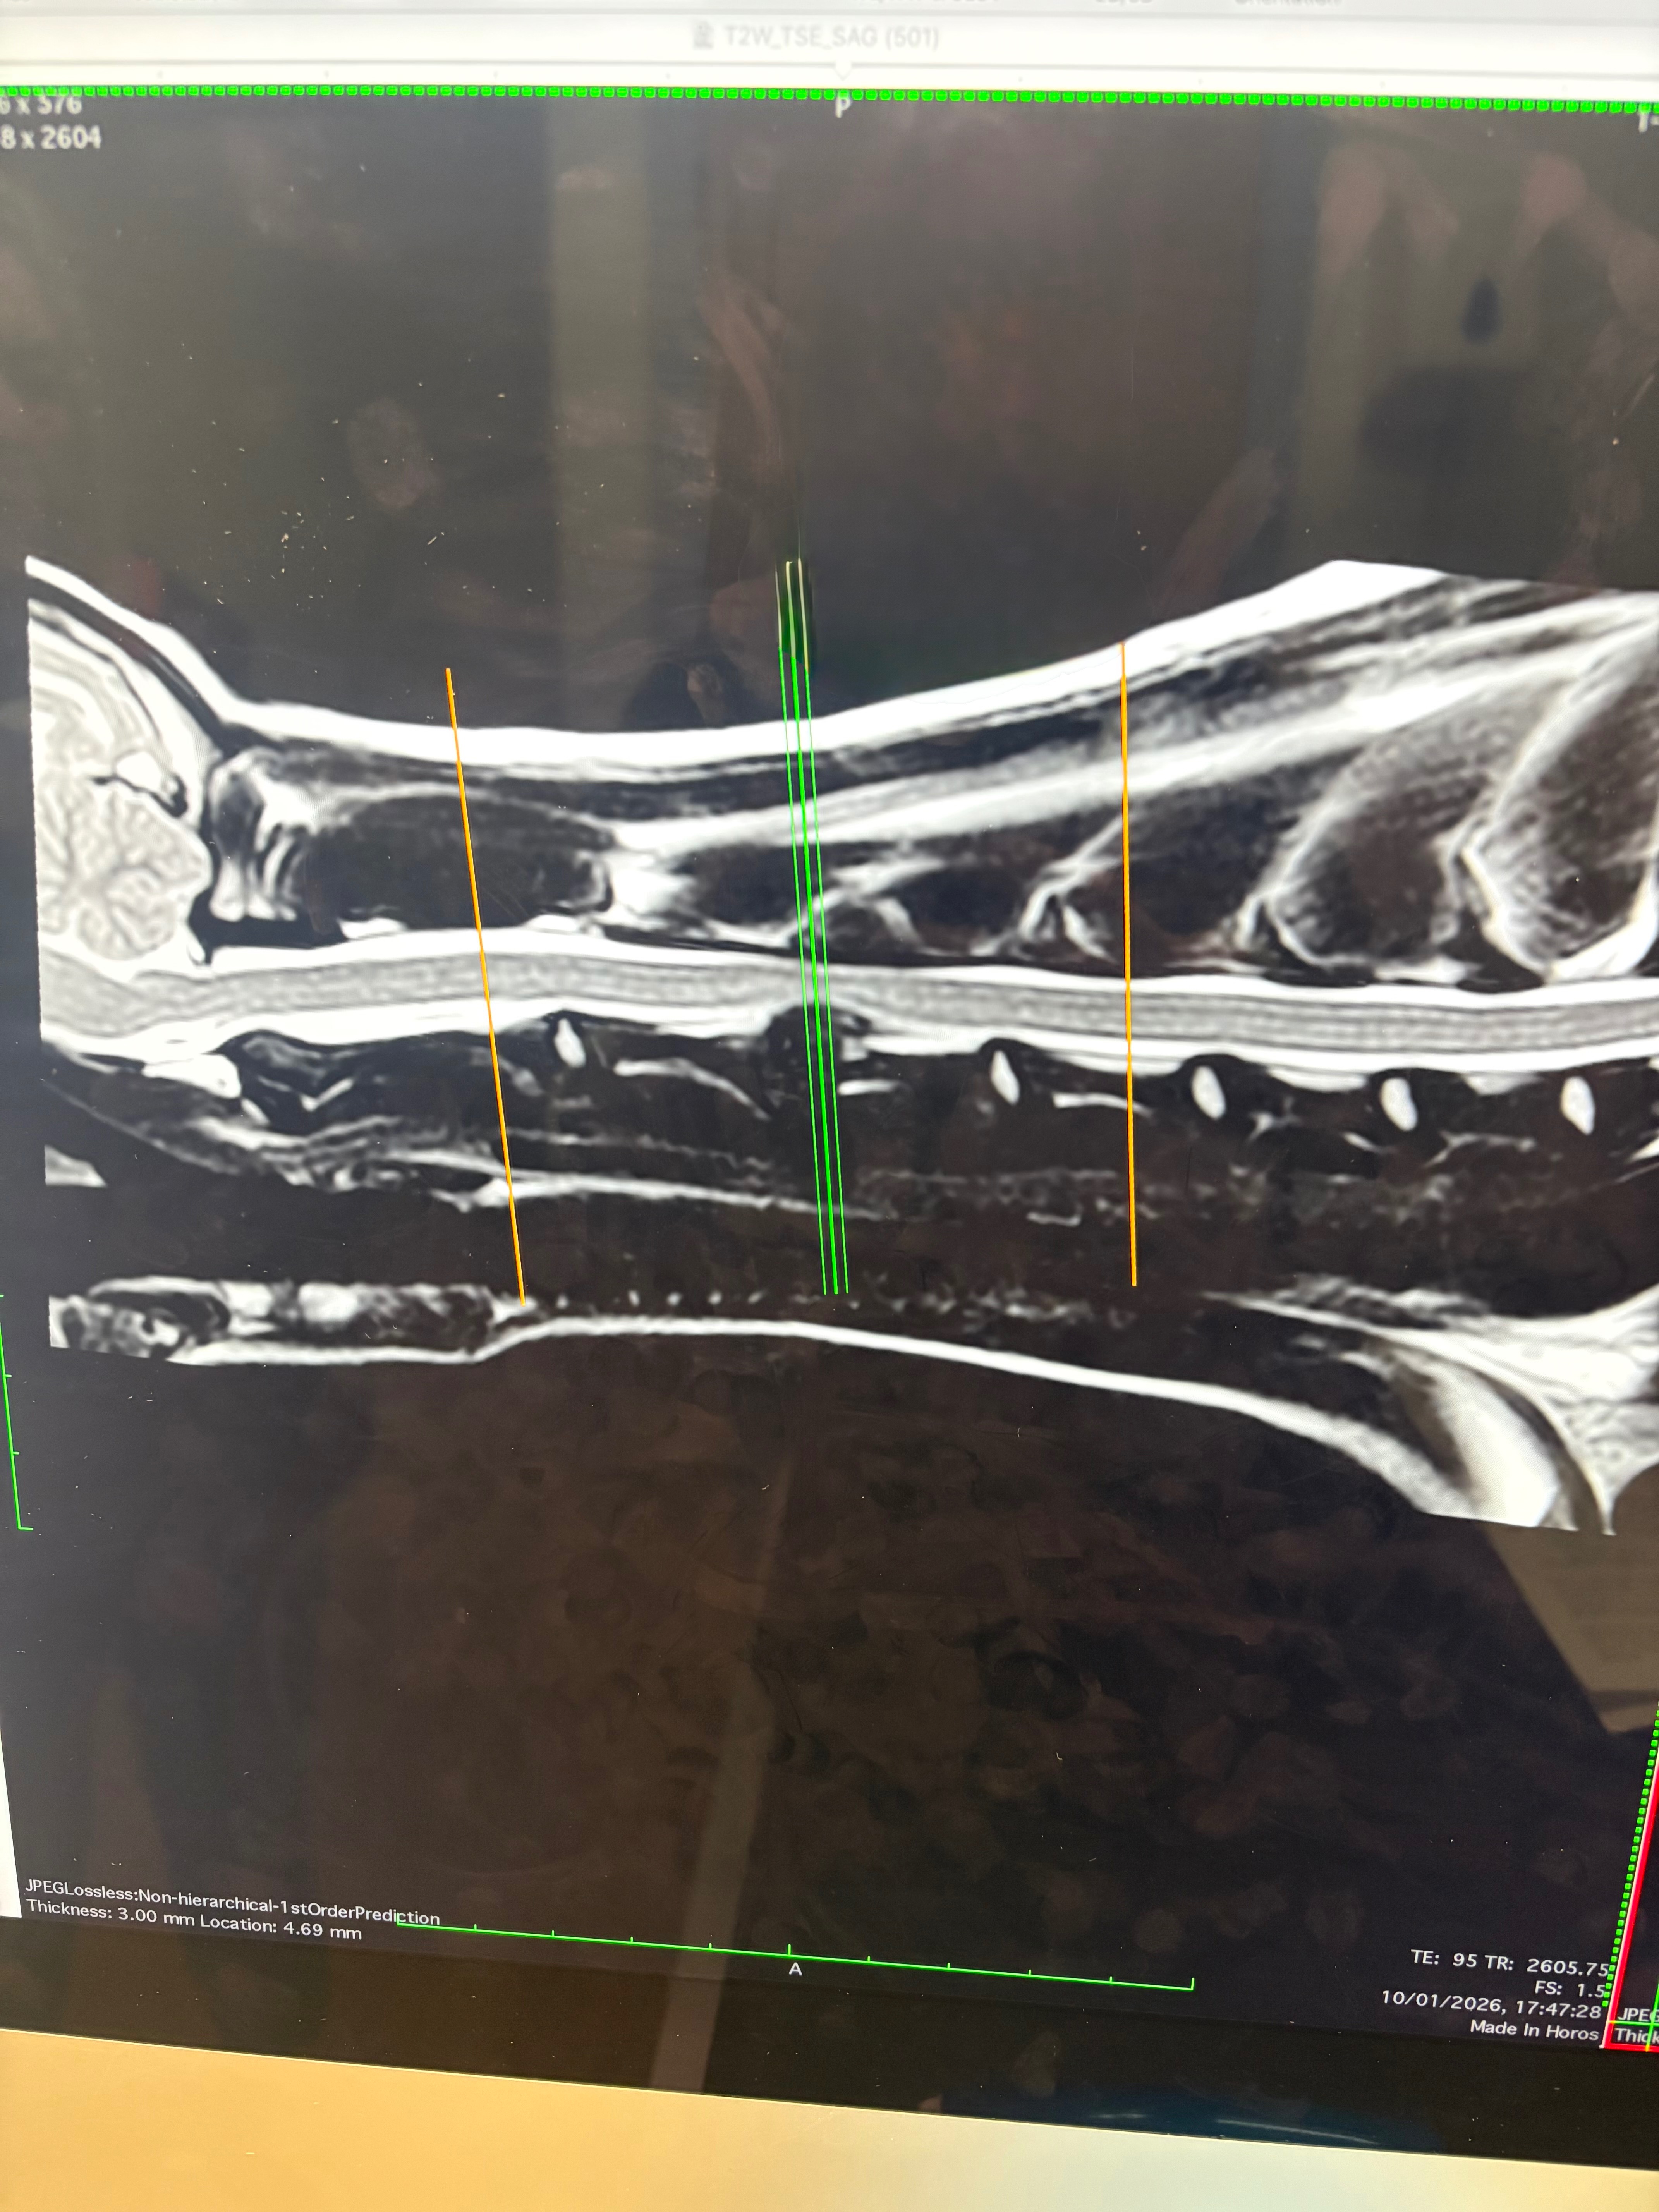

We’ve now been told Baxter urgently needs to be referred to a specialist for an emergency MRI, which has shown he has a slipped disc. The vets have said he needs surgery to give him the best chance of recovery and a pain-free life. Unfortunately, this surgery will cost a further £3,000, which my mum simply cannot afford.